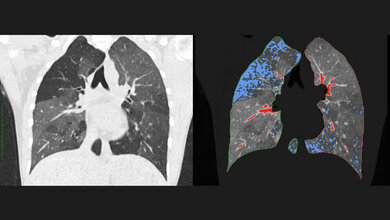

Zu diesem Zweck plant die Forschungsgruppe, verlässliche Daten über die klinischen und molekularen Eigenschaften von Patientinnen und Patienten zu gewinnen. Hierfür führen die Wissenschaftlerinnen und Wissenschaftler Daten aus Langzeitbeobachtung, systematischer Erfolgskontrolle, Biomaterialbanken, umfassende Labormessungen und umfangreiche Bildgebung von mehr als 6.000 Patienten zusammen. „Das Ergebnis besteht in der größten Datenbank zur COPD, die es bislang gibt“, hebt Schmeck hervor.

Diese Informationen sollen dabei helfen, ein Computerprogramm zu entwickeln, das die Therapieentscheidung der behandelnden Ärztinnen oder Ärzte unterstützt. Dabei kommt die neue Technologie des „maschinellen Lernens“ zum Einsatz. Die beteiligten medizinischen Zentren werden die Anwendung der Software erproben. „Das Verfahren wird die komplexe Therapieentscheidung bei COPD unterstützen und so einen Beitrag zur Kostensenkung leisten, aber auch Sterblichkeit und Behinderung sowie den Verlust von Lebensqualität vermindern helfen“, sagt Schmeck.